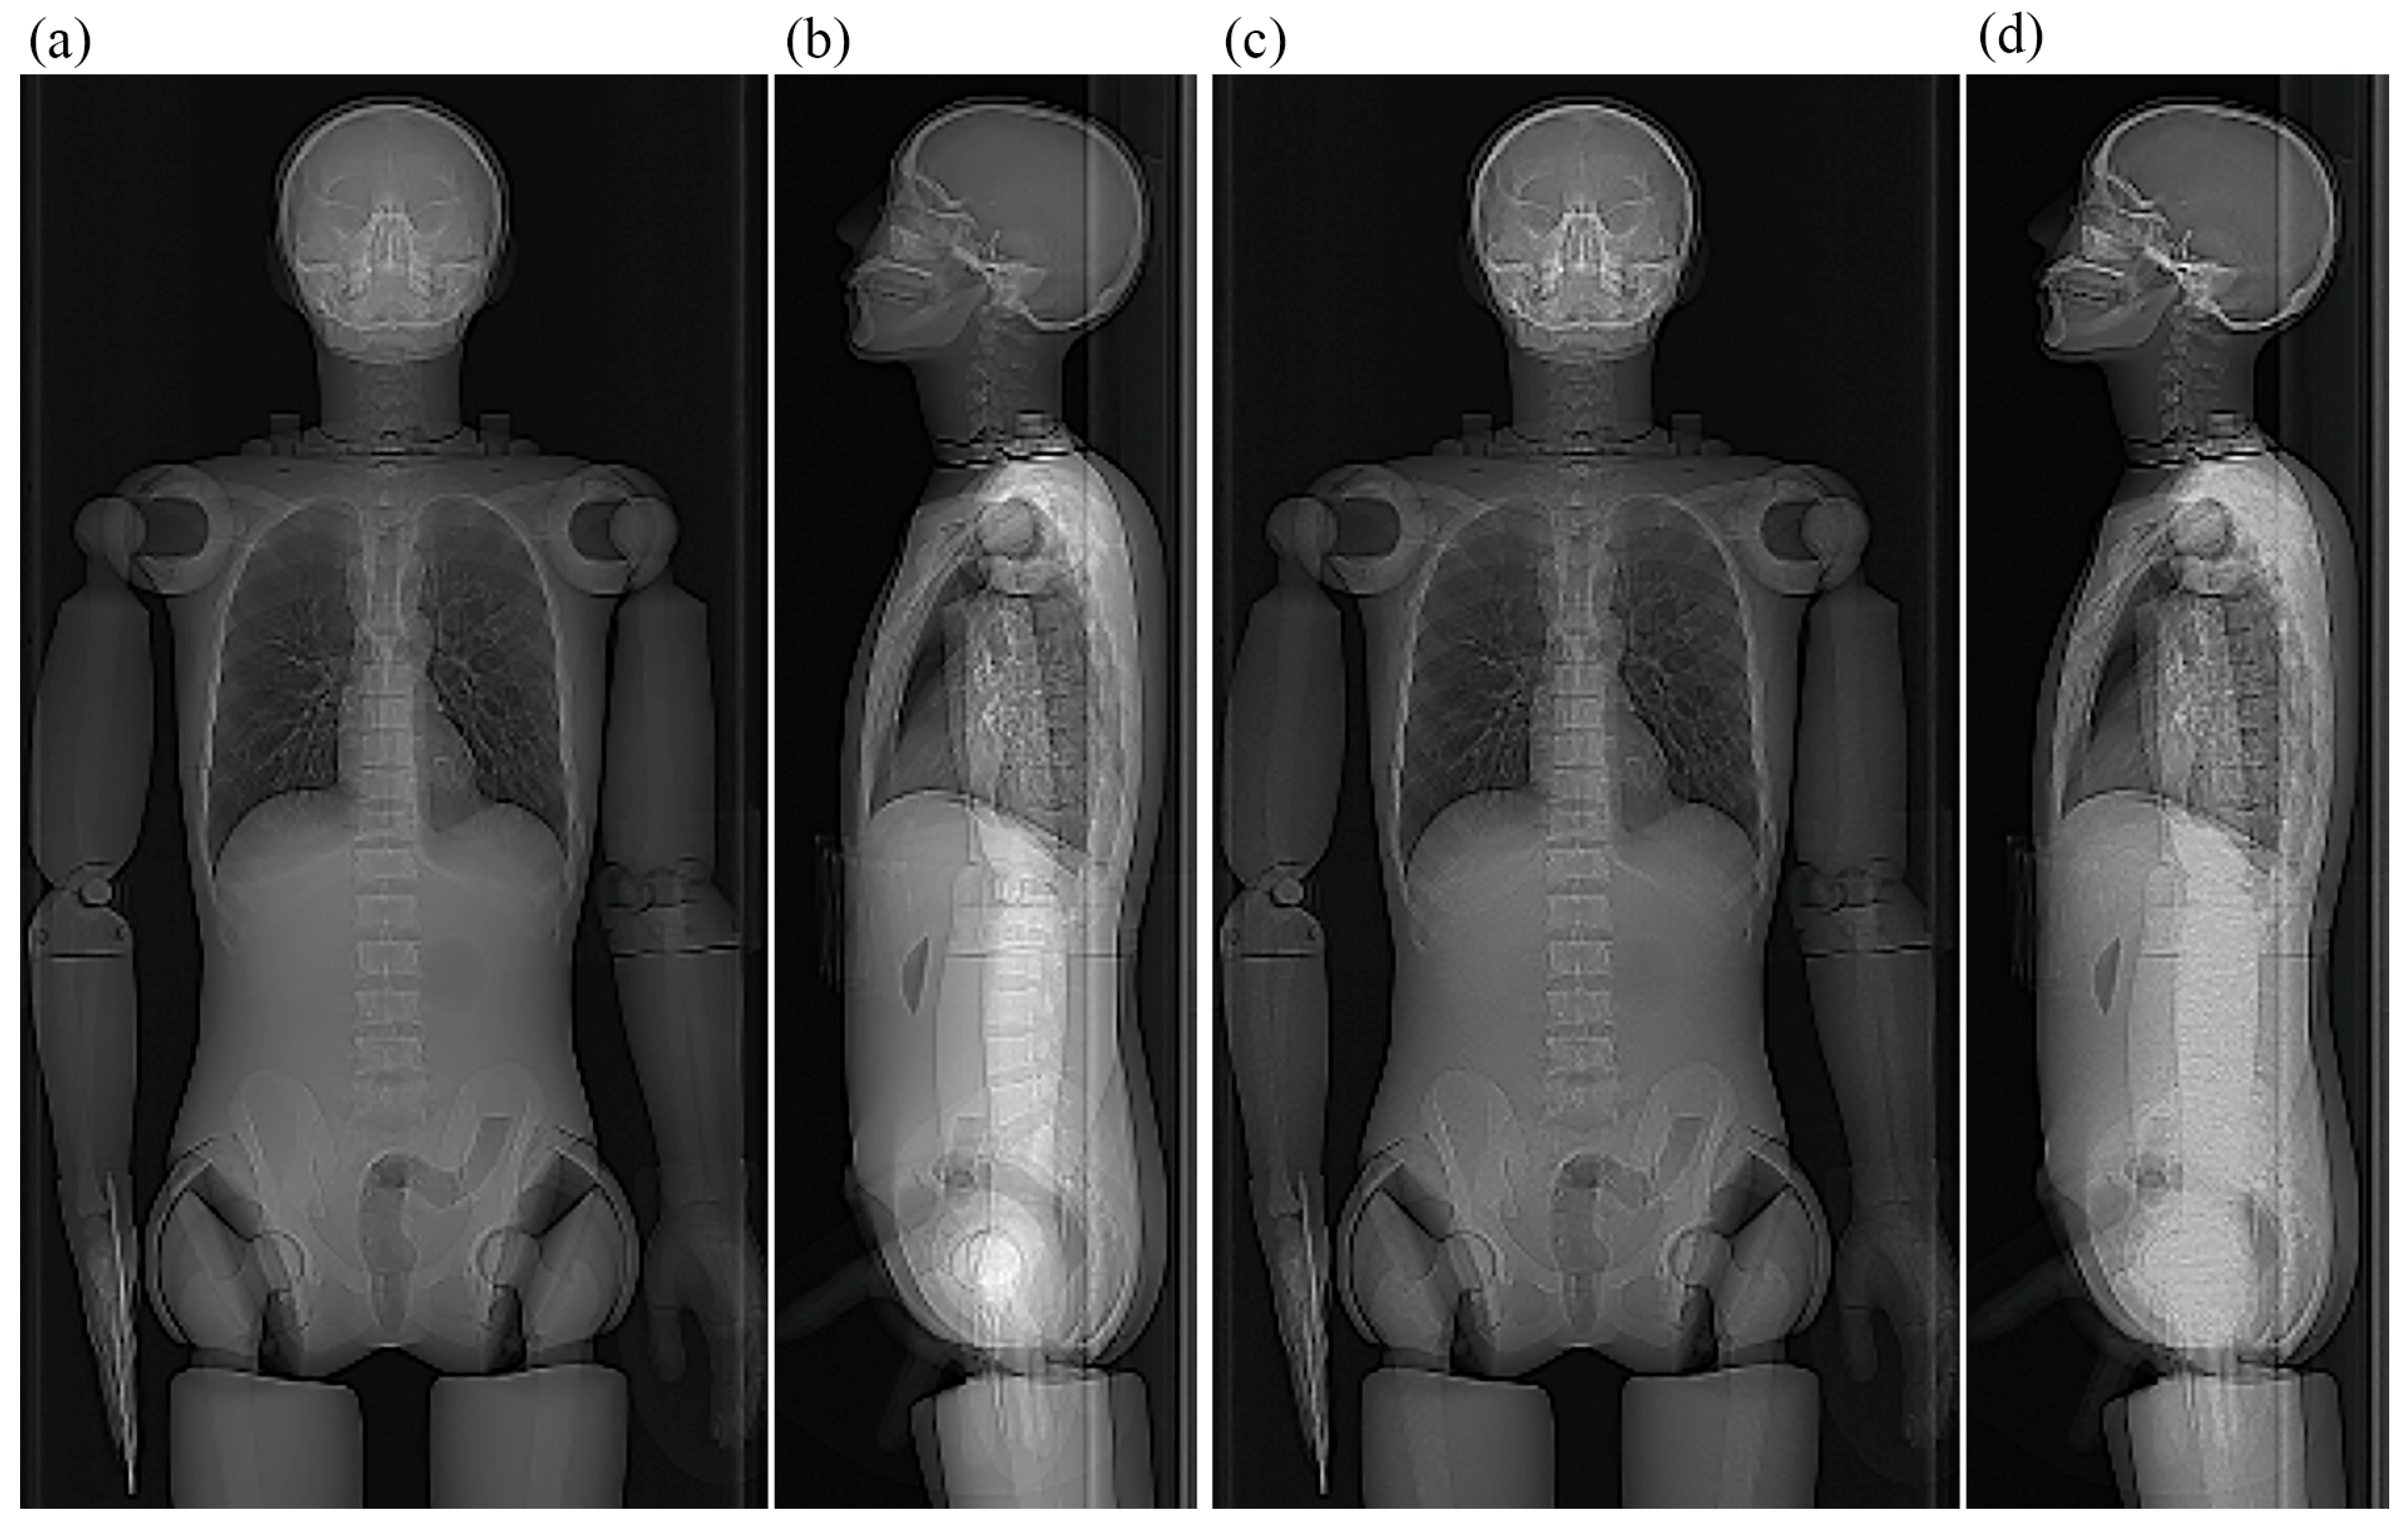

2.3. Effects of Vertical Positioning in Imaging the Anthropomorphic Phantom

2.4. Effects of Scout Imaging Parameters

3.2. Effects of Vertical Positioning in Imaging the Anthropomorphic Phantom

3.3. Effects of Scout Imaging Parameters